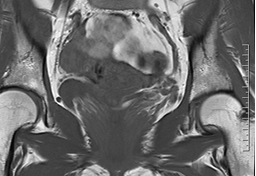

磁共振成像(MRI)能清晰显示子宫及其周围组织的解剖结构,有助于评估异常血管的走行、范围及其与邻近器官的关系,为临床诊断与治疗规划提供重要依据。

(子宫动静脉瘘MRI影像示意图)

典型MRI表现包括:

■ 子宫动静脉瘘MR-T1WI和T2WI序列子宫肌层或宫旁组织中可见卷曲扩张的流空信号,表现为无信号或低信号区域,类似血管的“流空效应”,提示存在异常扩张的血管团;

■ 增强T1WI序列病变部位可见迂曲的血管强化影,显示粗大的动脉血管与引流静脉直接交通,且无连接两者的毛细血管网;

■ 部分患者伴随子宫体积增大,子宫肌层交界区可能破坏,出现锯齿状或不规则的血流相关信号,提示病变累及肌层;

■ MRI可清晰显示动静脉瘘与周围组织(如宫旁血管、膀胱、直肠等)的关系,帮助评估病变范围及是否侵犯邻近器官。